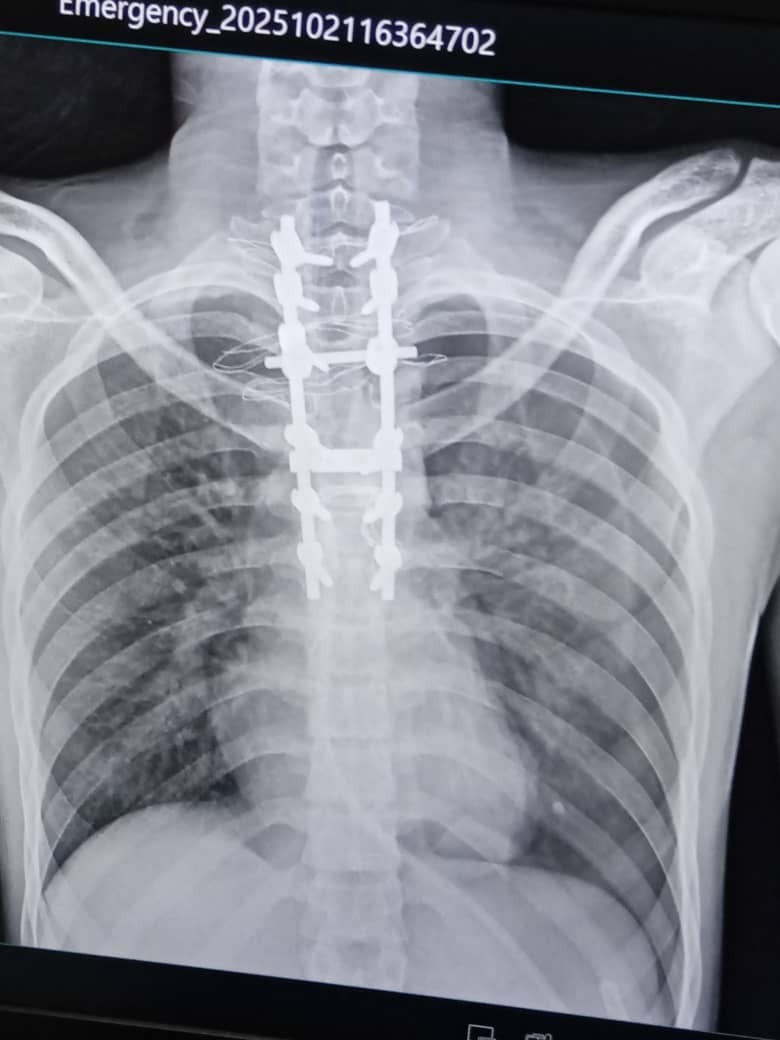

On the morning of October 17, 2025, Cesar David was riding his motorcycle to work when another driver suddenly cut him off. Cesar lost control and was thrown from his motorcycle onto the pavement at high speed, suffering a serious fracture to his spine and spinal cord. Cesar was admitted to Dr. Miguel Pérez Carreño Hospital in Caracas, Venezuela, after suffering severe polytrauma. His diagnosis is harrowing: ASIA A thoracic spinal cord injury, with fractures in the T3 and T4 vertebrae, which has required a decompressive laminectomy and extensive thoracic arthrodesis from T1 to T7. This surgical intervention represents only the beginning of a long recovery process.

Cesar fue ingresado al Hospital Dr. Miguel Pérez Carreño en Caracas, Venezuela, tras un politraumatismo severo. Su diagnóstico es estremecedor: Traumatismo raquimedular dorsal ASIA A, con fracturas en las vértebras T3 y T4, lo que ha requerido una laminectomía descompresiva y una artrodesis dorsal extensa desde T1 hasta T7. Esta intervención quirúrgica representa solo el inicio de un largo proceso de recuperación.